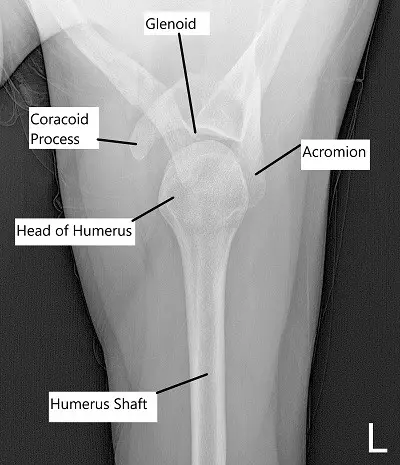

Axial view of left shoulder.

The Glenohumeral or the real shoulder joint is made up of the articulation of the ball of the head of the arm bone called the humerus into the cup of the shoulder blade called the scapula.

The cup makes only 1/8th of the circumference of the shoulder and hence the shoulder joint is seemingly unstable, especially if compared to other large ball and socket joints of the body that is the hip joint. The joint can be involved in arthritis and well as fractures and sprains